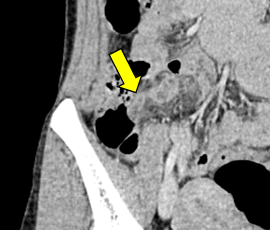

[急性虫垂炎] 手術:腹腔鏡下虫垂切除術

急性腹症のため救急受診。精査の結果、急性虫垂炎および限局性腹膜炎と診断。緊急手術(腹腔鏡下虫垂切除術)を施行した。病理診断結果は急性虫垂炎であった。

CT画像